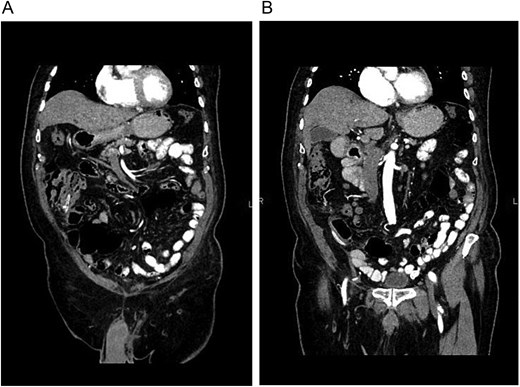

Lower gastrointestinal bleeding due to a perforation of the cecum wall, caused by drainage, was the final diagnosis.

A new contrast-enhanced CT (Fig. 2A and B) was performed, confirming that the drain was perforating the bowel without pneumoperitoneum or inflammation, and, as the patient remained asymptomatic, a conservative management of the drain perforation was decided and treated as a cecal fistula. The drain was left in place for 10 days and removed due to low and serous output (Fig. 3). The patient was discharged without complications and remained on close follow-up. One year after surgery, he is doing well.

(A) CT, the drain is seen within the colon. (B) CT, no free air or fat stranding is seen around the colon or drain.